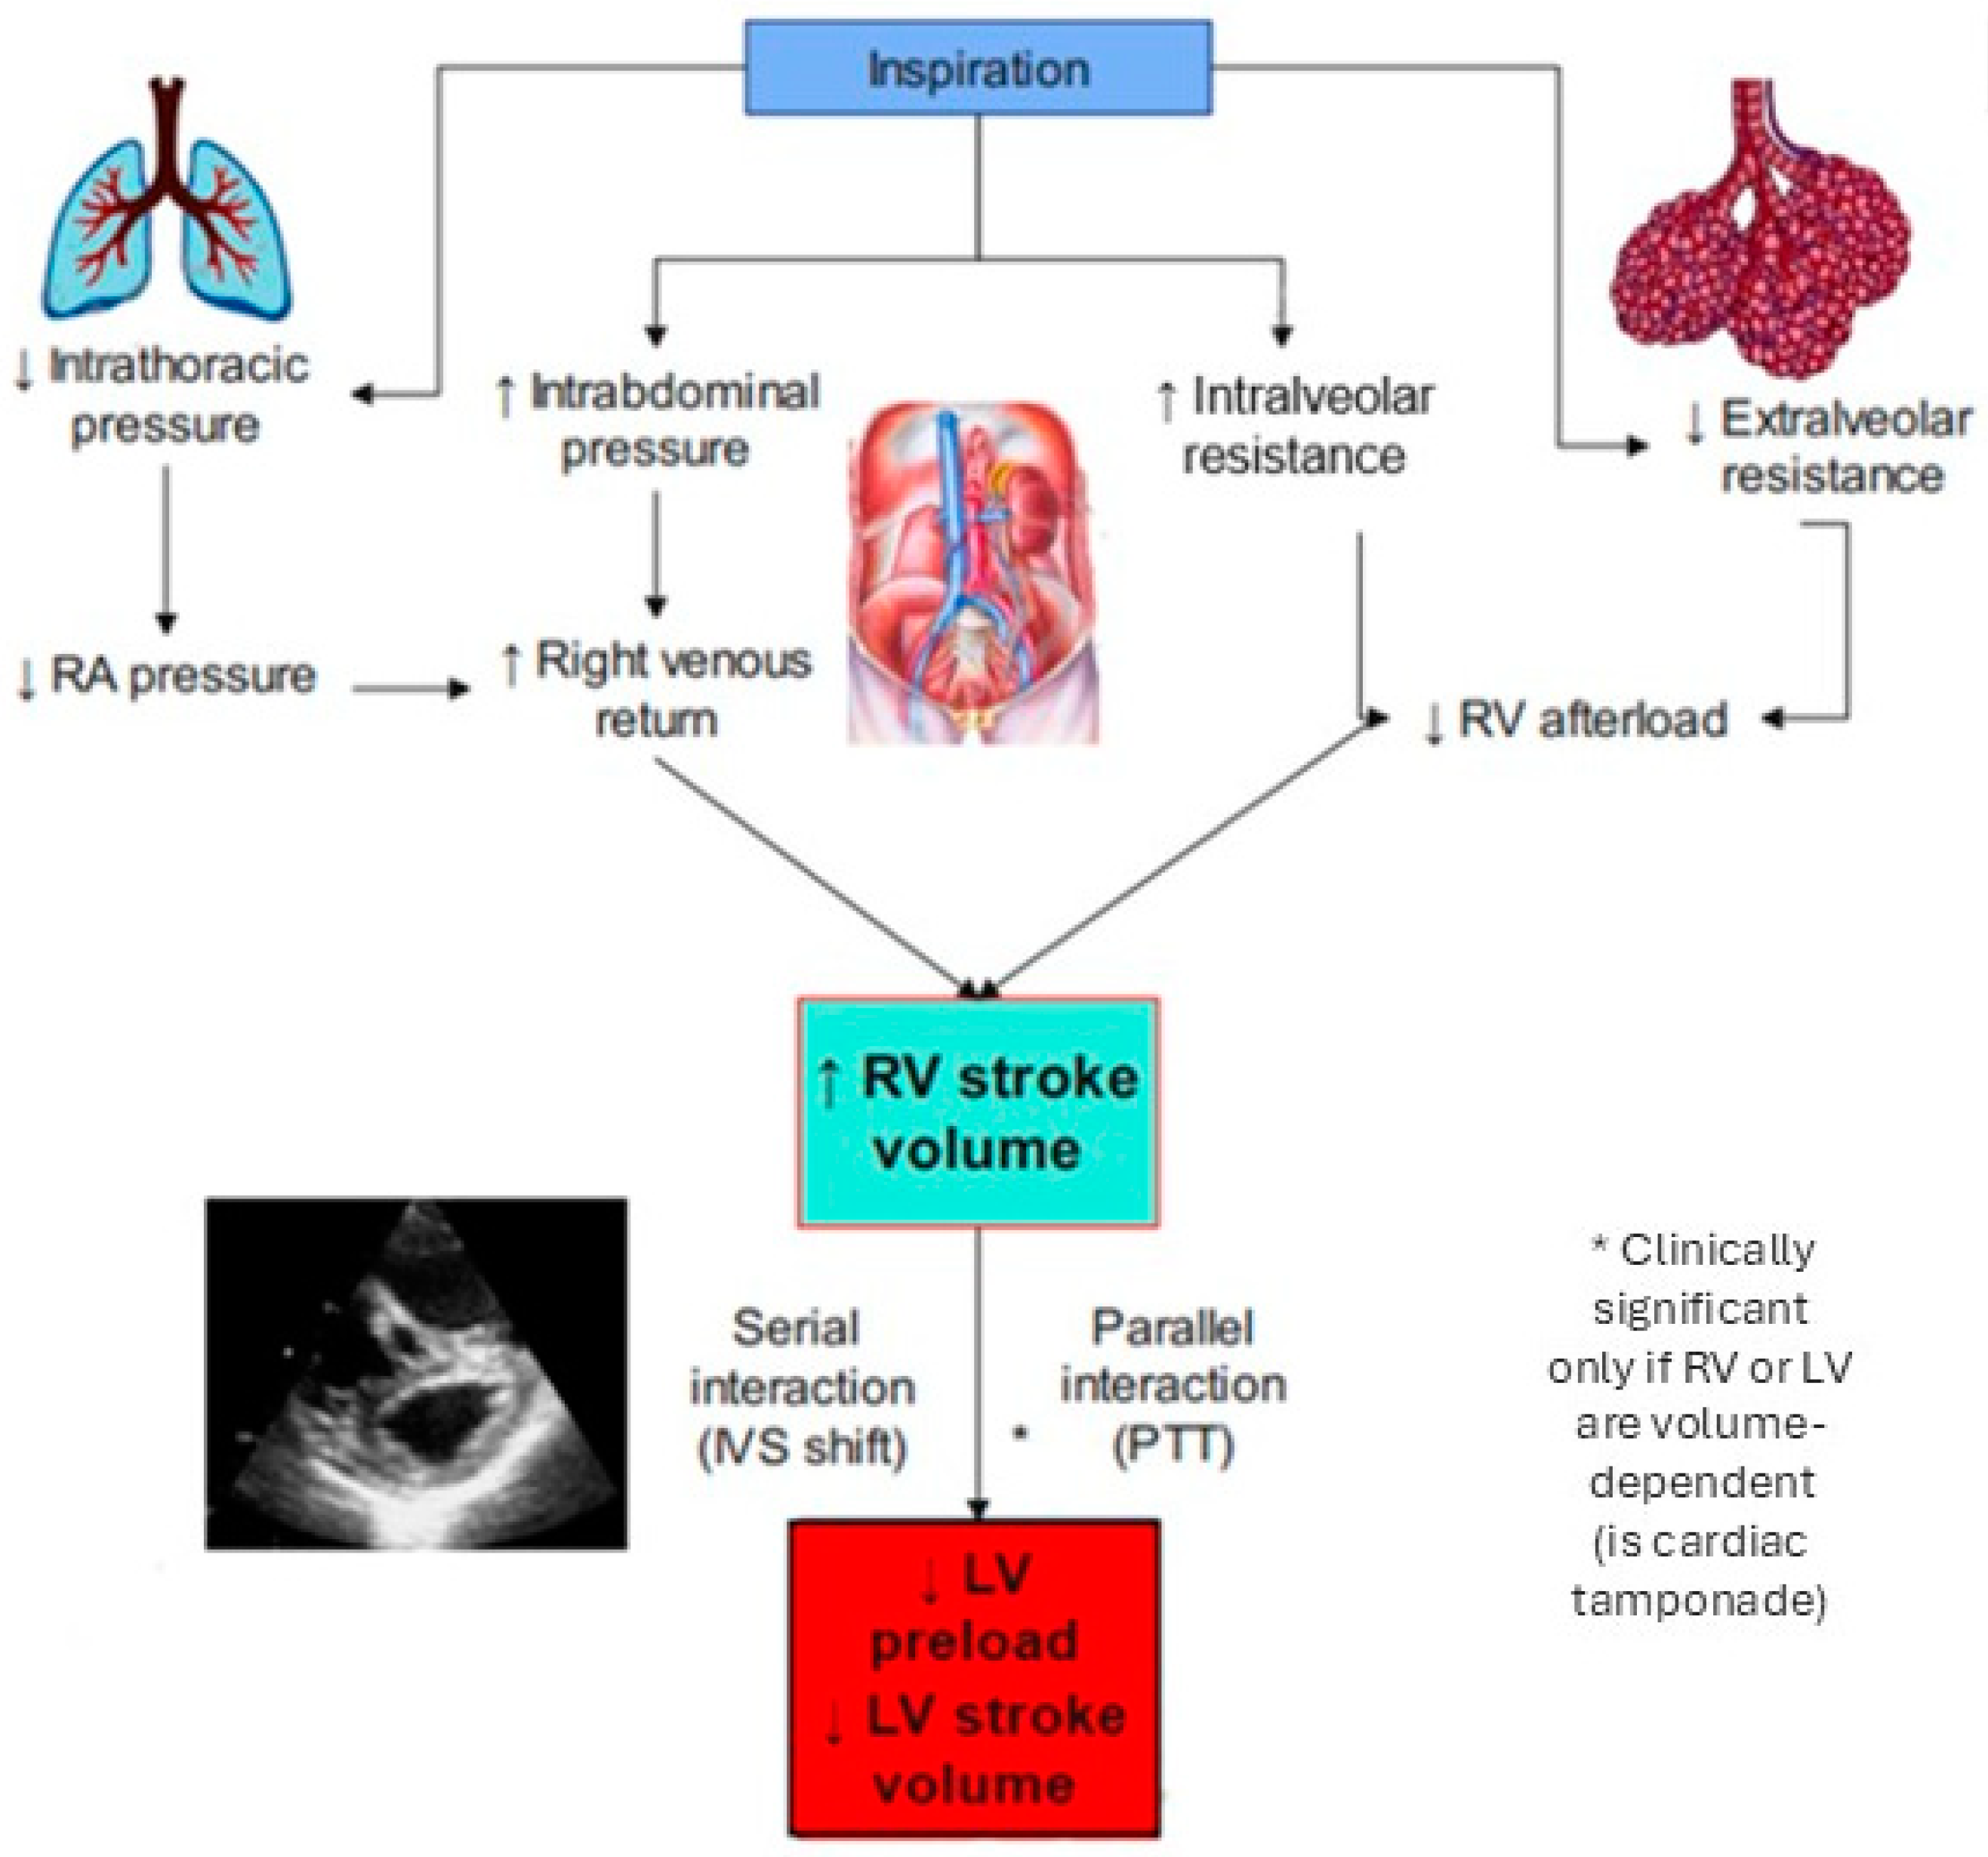

2. Heart–Lung Interaction in Spontaneous Ventilation